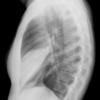

Case 2 Lingular pneum PA

Date: 04/17/2005

Views: 6019